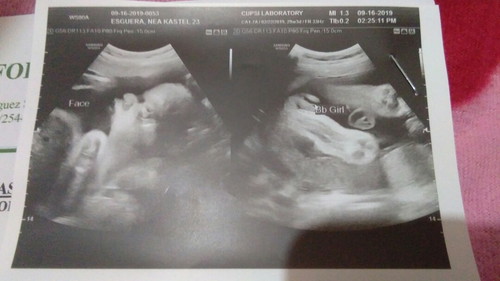

ultrasound pelvis and gender reveal.. ??

Mga momies.. plz see the photo kung ok lng ba kondisyon ni baby girl ko. ☺??? then kung ok lng ba result nga ultrasound sa porma ng face ng baby ko.. thanks..

Ok ra sya sis. Ayaw tanaw sa photo kay d ta kasabot ana haha. Sa last pic tanawa.